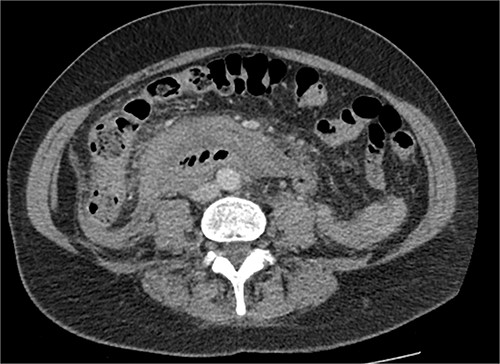

After further discussion with the reporting radiologist, a magnetic resonance imaging (MRI) was performed, which confirmed the presence of an acute periduodenal hematoma surrounding D2 and D3, lying in the retroperitoneal space, anterior to the right perirenal space. Etiology was uncertain. No abnormal enhancement within the bowel to suggest a bowel wall lesion or infiltrating mass (Figs 3 and 4).

MRI abdomen, coronal view. T2 hypointense, T1 iso to hyperintense material surrounding D2/D3 without enhancement in keeping with hemorrhage. No vascular or bowel wall lesion identified.